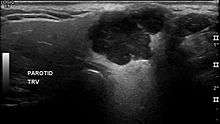

In terms of imaging studies, ultrasound can determine and characterize superficial parotid tumors. Certain types of salivary gland tumors have certain sonographic characteristics on ultrasound.[4] Ultrasound is also frequently used to guide FNA or core needle biopsy.